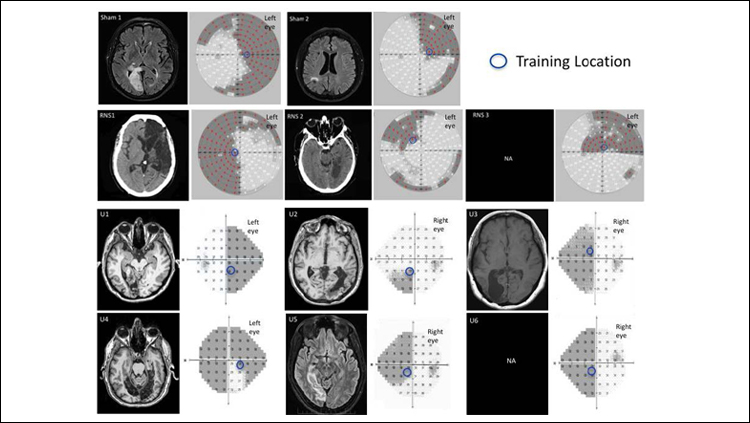

May 28, 2019Press ReleaseA combination of visual training and a recently developed brain stimulation technique boosts learning in healthy adults and cortically blind patients, according to research published in JNeurosci.